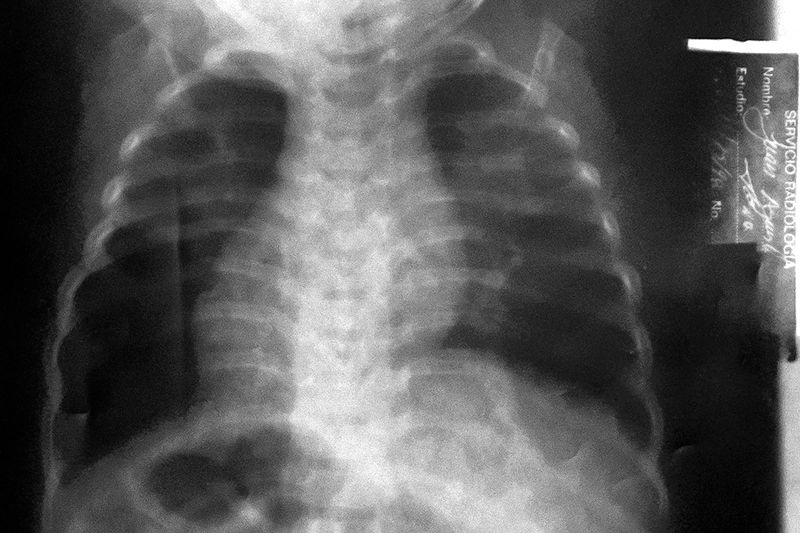

The chance that you build a bond with a place that you leave around your first birthday is small. And it doesn't get bigger if your body and mind have suffered considerable scars because you were born 14 weeks early.